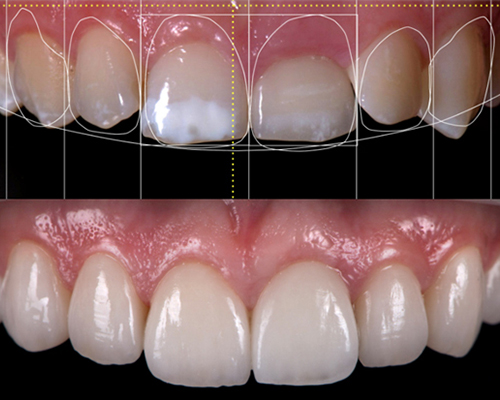

Smile DesignSmile Design

Smile DesignSmile Design